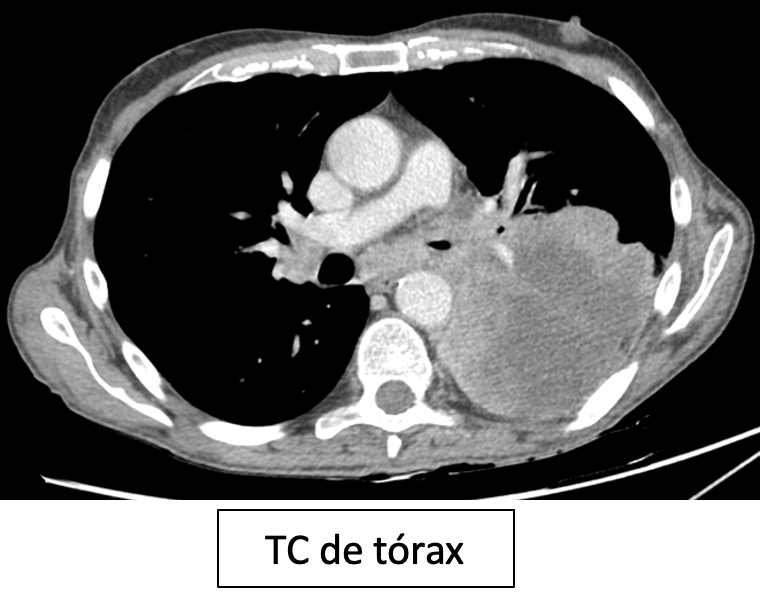

Masa pulmonar posterior izquierda heterogénea. Mediastino e hilio contralateral normales.

B

Masa pulmonar posterior izquierda homogénea. Mediastino e hilio contralateral normales.

C

Masa pulmonar posterior izquierda heterogénea. Ocupación mediastínica e hiliar contralateral.

D

Masa pulmonar posterior izquierda homogénea. Ocupación mediastínica e hiliar contralateral.